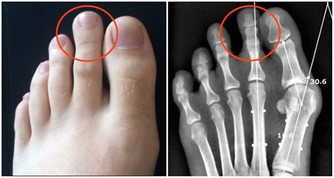

如果出現角膜色素環,這是肝豆狀核變性患者的主要特徵。

據統計,此病的遺傳性發生率可佔此病患者的90%。

用肉眼可見環繞角膜、邊緣寬約2-3mm的黃綠色、藍綠色或棕黃色環狀帶。